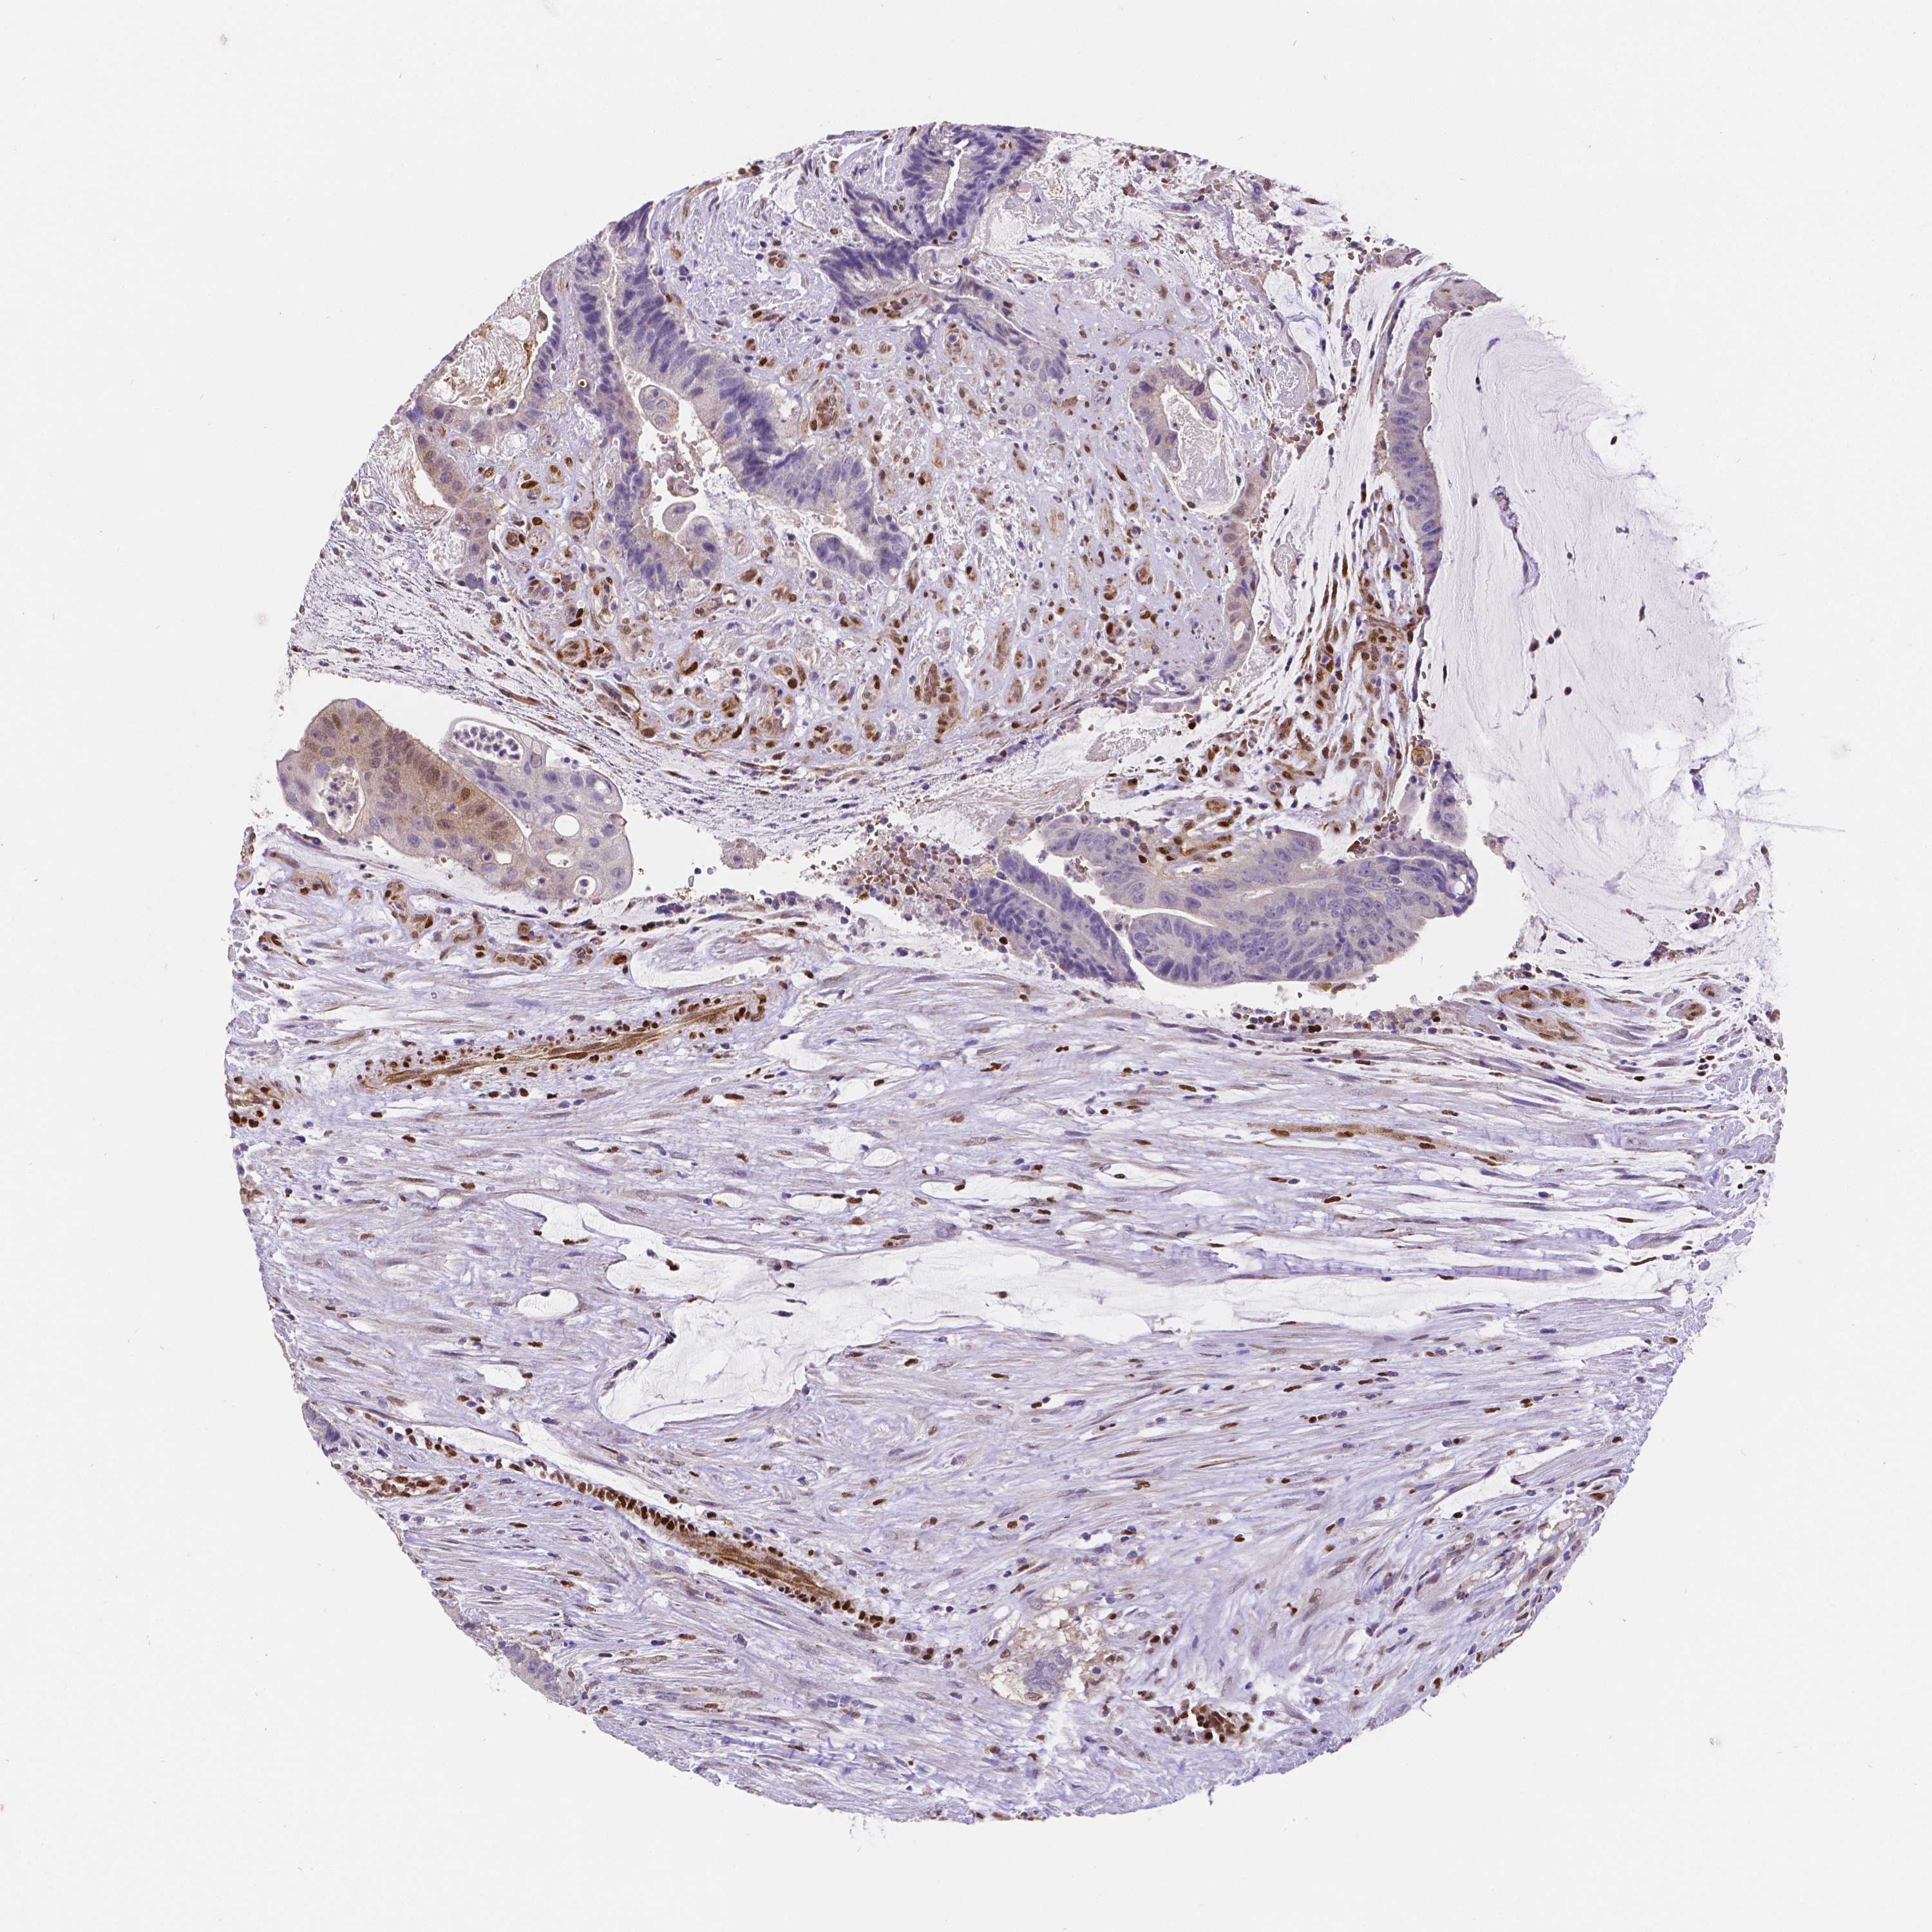

COAD TCGA COAD VALIDATION READ TCGA READ VALIDATION PROTEIN COAD CPTAC PROTEIN EXPRESSION

ANTIBODIES

AND

VALIDATION